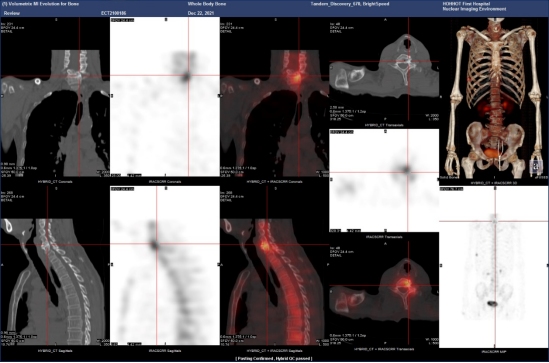

(病例一)患者,男,39岁,右肺门中央型肺癌T3N2MX(IIIB期),为明确是否有骨转移来我科就诊。MIP图示:额骨右侧、C6、T12、左侧第6肋,右侧第7、8肋多发小片状放射性摄取增高灶,SPECT/CT融合图示:额骨右侧、C6、T12、左侧第6肋,右侧第7、8肋未见明显骨质破坏。结合肺癌病史,考虑额骨右侧、C6、T12、左侧第6肋,右侧第7、8肋多发骨转移。如下图: